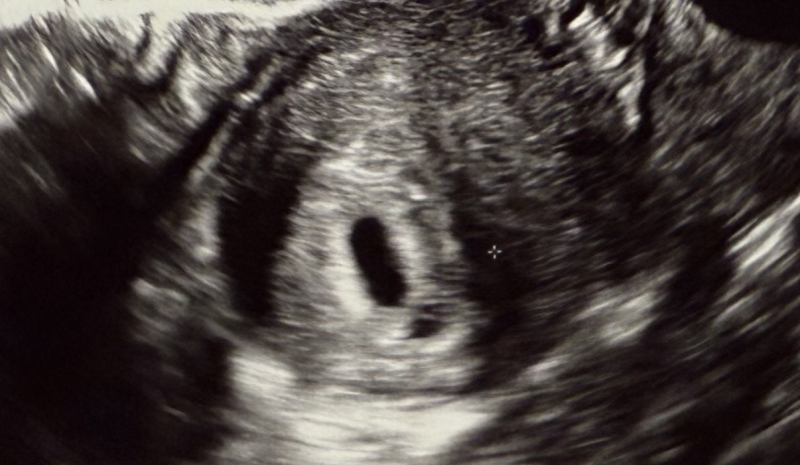

5週0日にいただいたエコーを確認すると、縦長の胎嚢(8.8mm)の下辺りに黒く抜けている部分があることに気づきました。

特にその場や診察では指摘されませんでしたが、胎嚢がもう一つあるように見えます。

体外受精をされていて、戻されたのは1個だけのようでしたら、お写真のエコーでの写りで見ると双子ちゃんの可能性は低いのではと思いました。二つに分かれているようにも見えます。